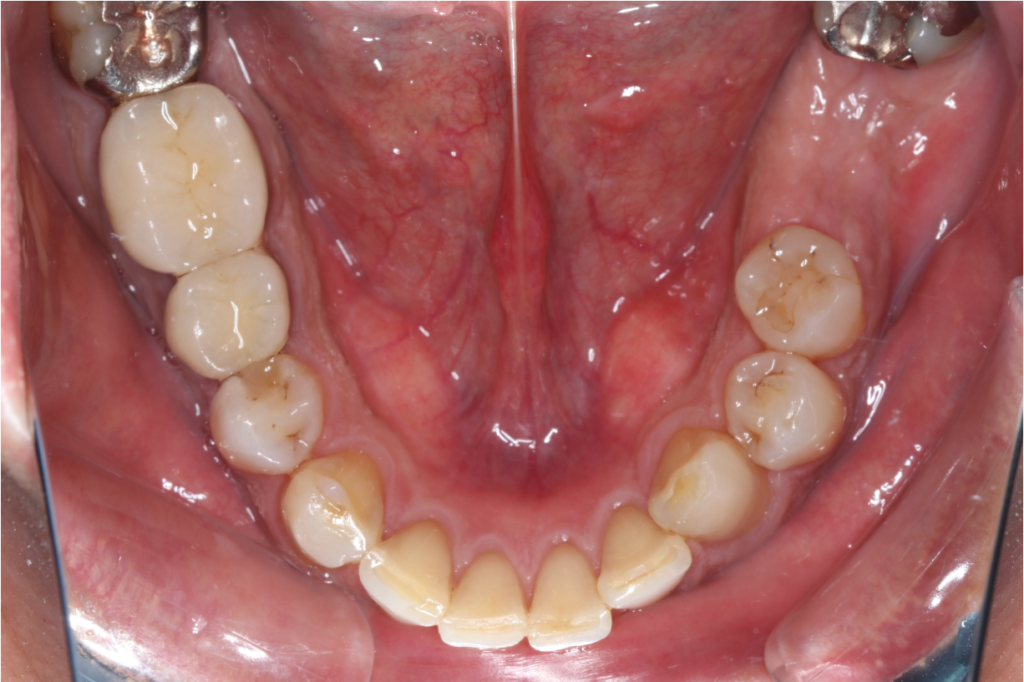

インプラント症例③

年齢 50代女性

治療期間 4ヶ月

インプラントメーカ ストローマンインプラント

治療内容 カスタムアバットメント、上部ジルコニア

治療箇所 左下5番、6番 右下6番、7番

治療費用 1,600,000円